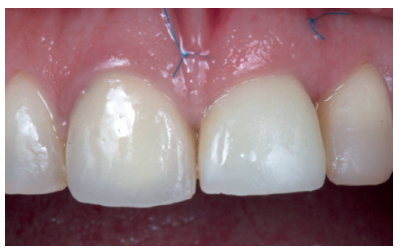

Utilizando el escáner 3Shape®, se realizó un pre-escaneado intraoral, primero con la corona dentosoportada colocada, para obtener la anatomía del incisivo central, y después sin ésta, escaneando así el perfil de emergencia del resto radicular; se informó al laboratorio de la modificación del perfil critico, corrigiendo así la recesión existente respecto al 1.1 (Figuras 5-7). Este escaneado sirvió a su vez para la toma de color del futuro provisional7,8. El archivo STL fue enviado al laboratorio protésico para elaborar la prótesis provisional tipo Maryland, en polimetil-metacrilato (PMMA), con dos apoyos en los bordes incisales de los dientes adyacentes para asegurar su correcto posicionamiento que, según la planificación previa, serviría como diente provisional, así como de guía quirúrgica para la inserción del IOI en la posición protésica idónea, evitando así posibles problemas futuros a nivel protésico o en la integridad de los tejidos blandos y duros de la región vestibular (Figuras 8 y 9).

Tras 14 semanas se retiró el provisional, apreciando una correcta posición del margen gingival, con una cobertura de la recesión del 100%, un mantenimiento íntegro de las papilas y un correcto perfil de emergencia (Figuras 14 y 15). No obstante, desde una vista oclusal se evidenció una falta de volumen vestibular respecto al diente adyacente. Se comenzó a trabajar con la corona provisional, con incrementos progresivos de composite en el perfil subcrítico, hasta conseguir un volumen similar al diente 1.1. Estos incrementos fueron realizados cada 15 días (Figura 16)13.